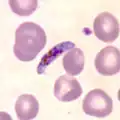

Plasmodium falciparum, the causative agent of malaria, infecting blood cells

Plasmodium falciparum, the causative agent of malaria, infecting blood cells -